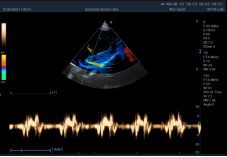

8P2MA ● 3.5-15.0MHz ● Single crystal phased array probe ● For Cardiology of felines |

3P2PA ● 1.0-6.5MHz ● Phased array probe ● For Cardiology of big-sized canines |

5P1PAA ● 2.5-13.0MHz ● Phased array probe ● For Cardiology of small and medium-sized canines |

6C1PDA ● 2.5-13.5MHz ● Micro convex array probe ● For Abdomen, Cardiology, Reproduction |